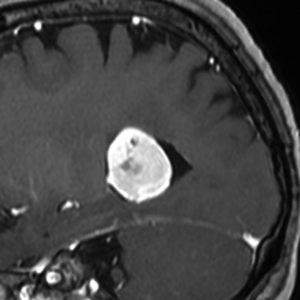

若い女性に偶然発見されたものです。直静脈洞と静脈洞交会の接合部あたりに発生したもので,静脈洞はほぼ閉塞に近い所見でした。しかし,この部分の静脈洞は,テント硬静脈側副路が発達することがあるので,硬膜を含めた積極的な摘出をすることは絶対にできません。もしほんの少しでも流れがある直静脈洞を閉塞させると短時間に脳死になるような脳静脈圧亢進が生じる可能性があるからです。静脈洞内に少し取り残して(右下の矢印)手術を終了しました。手術後には定位放射線治療を行って再増大を防ぎます,